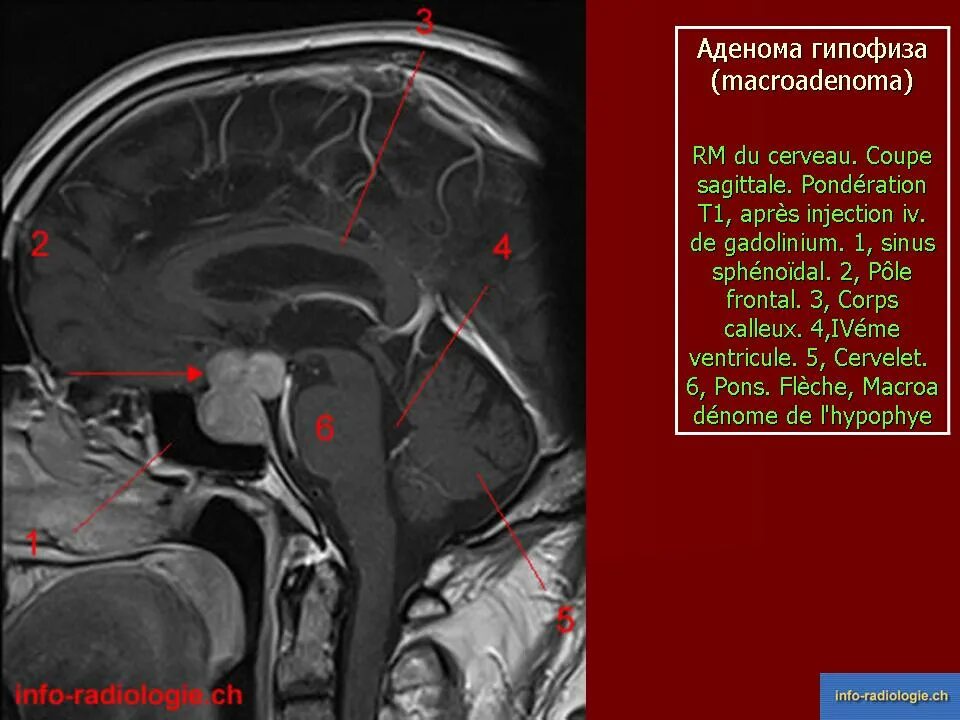

Опухоль гипофиза